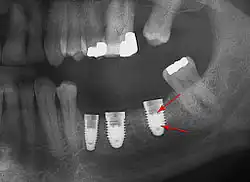

Beyond the possibility of mechanical failure[73] which may be due to poor prosthetic fitment, wear and tear, or user-induced actions such as bruxism, dental implants are also subject to peri-implant mucositis and peri-implantitis, where gum tissue and bone mass around the implant are resorbed, and the implant gradually becomes loose, and has to be removed.[74][75] In addition, although titanium is generally well tolerated by the body, there have been cases where the build-up of titanium particles released by the implant may cause systemic inflammatory response.[76] Because there is no dental enamel on an implant, it does not fail due to cavities like natural teeth. While large-scale, long-term studies are scarce, several systematic reviews estimate the long-term (five to ten years) survival of dental implants at 93–98 percent depending on their clinical use.[2][3][4] During initial development of implant retained teeth, all crowns were attached to the teeth with screws, but more recent advancements have allowed placement of crowns on the abutments with dental cement (akin to placing a crown on a tooth). This has created the potential for cement, that escapes from under the crown during cementation to get caught in the gingiva and create a peri-implantitis (see picture below). While the complication can occur, there does not appear to be any additional peri-implantitis in cement-retained crowns compared to screw-retained crowns overall.[77] In compound implants (two stage implants), between the actual implant and the superstructure (abutment) are gaps and cavities into which bacteria can penetrate from the oral cavity. Later these bacteria will return into the adjacent tissue and can cause periimplantitis.